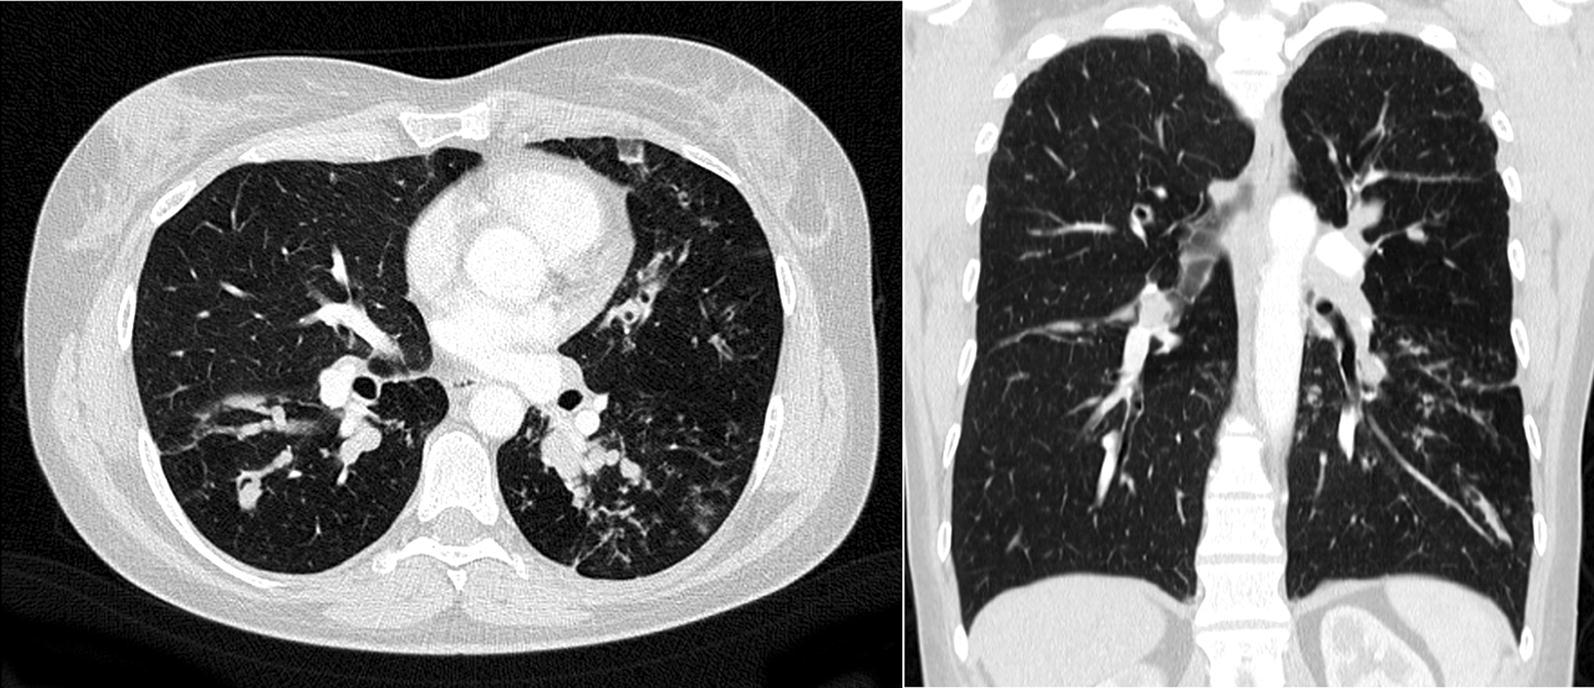

Here, we report the case of a 49-year-old woman with severe asthma and ABPA, who was uncontrolled despite maximum inhalative therapy, anti-IL5-Rα antibody and continuous oral steroid therapy. Moreover, trials of itraconazole as well as omalizumab showed insufficient efficacy. Lung function revealed peripheral obstruction. FeNO and IgE were increased, eosinophils were suppressed under treatment while marked increases had been documented previously. Switching to dupilumab led to a complete resolution of pulmonary symptoms, resolution of exacerbations and complete withdrawal of oral steroids. A drastic improvement in lung function was noted, with an increase in FEV1 of almost 1 l. FeNO was normalized and IgE strongly reduced.

在此,我们报告一例49岁患有重度哮喘和ABPA的女性病例,尽管接受了最大剂量的吸入治疗、抗IL-5Rα抗体治疗及持续口服类固醇治疗,病情仍未得到控制。此外,伊曲康唑和奥马珠单抗的试验显示疗效不足。肺功能检查显示外周性气道阻塞。呼出一氧化氮(FeNO)和IgE升高,治疗期间嗜酸性粒细胞受到抑制,而之前记录显示其显著升高。改用度普利尤单抗后,肺部症状完全缓解,病情加重情况得到缓解,口服类固醇药物完全停用。肺功能有显著改善,第一秒用力呼气容积(FEV1)增加近1升。FeNO恢复正常,IgE大幅降低。